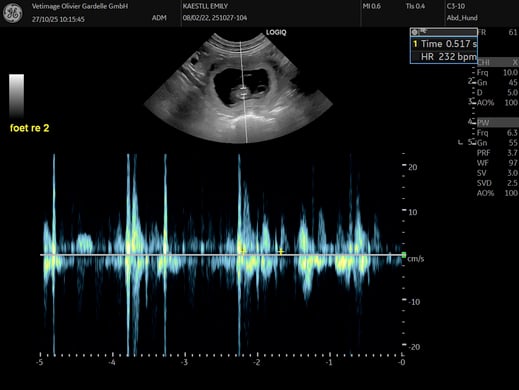

27. Oktober 2025

Von der Haushalthilfe zum Mami

Beim E- und F-Wurf hat Emily schon ausgiebig Ihre Eignung als Hilfsmami gezeigt. Und schon bald wird sie selbst Mami sein. Emily ist trächtig und wenn alles gut geht, werden wir Ende November Welpen im Haus haben. Wir freuen uns!

Weitere Details zur Wurfplanung gibt es HIER